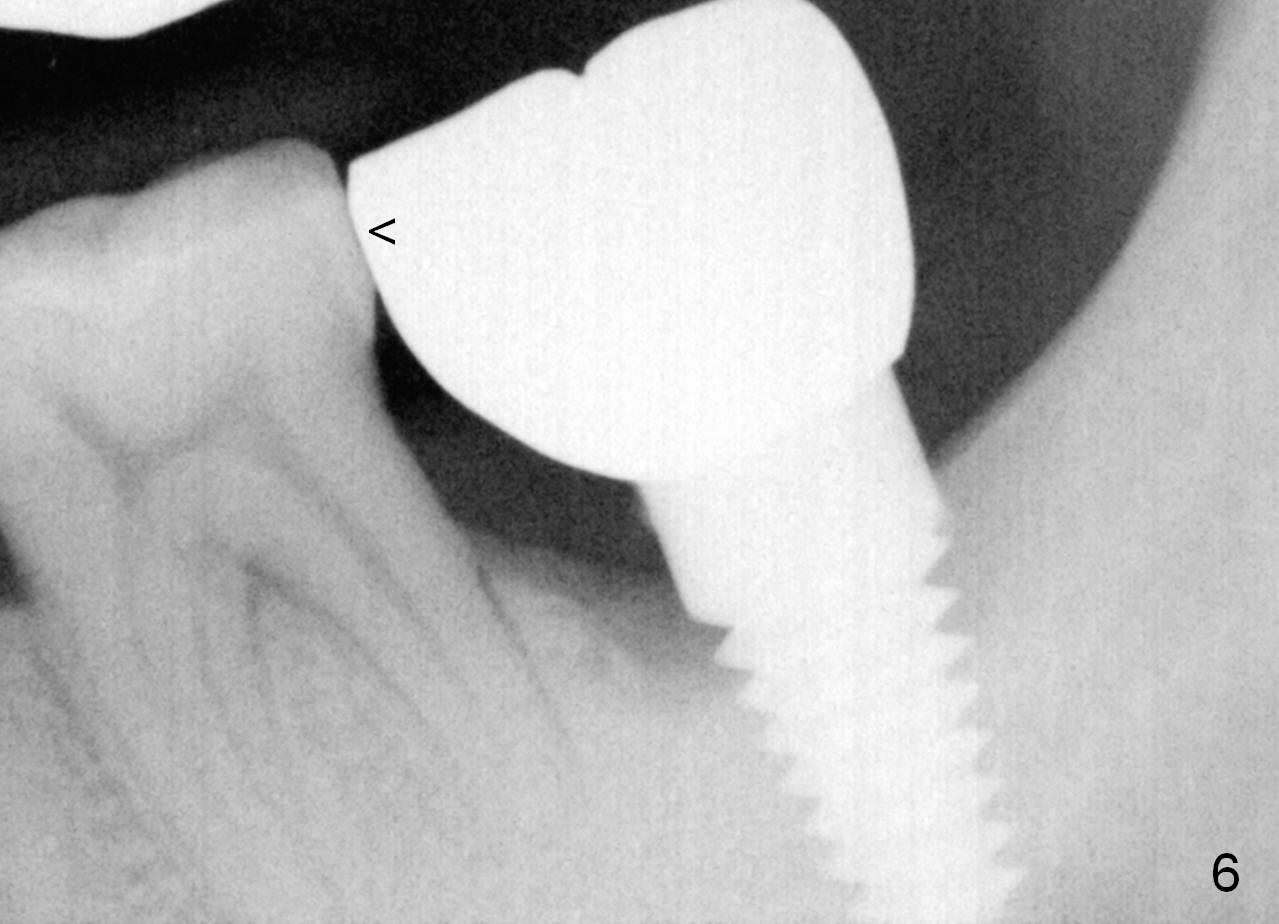

When a new crown is fabricated and cemented, the contact seems to be normal (Fig.6 (trimmed from a bitewing) <). The bone loss does not look as severe as before (Fig.5). Clinically, the gingiva is firmly attached to the implant without sign of inflammation. The case will be closely followed up.